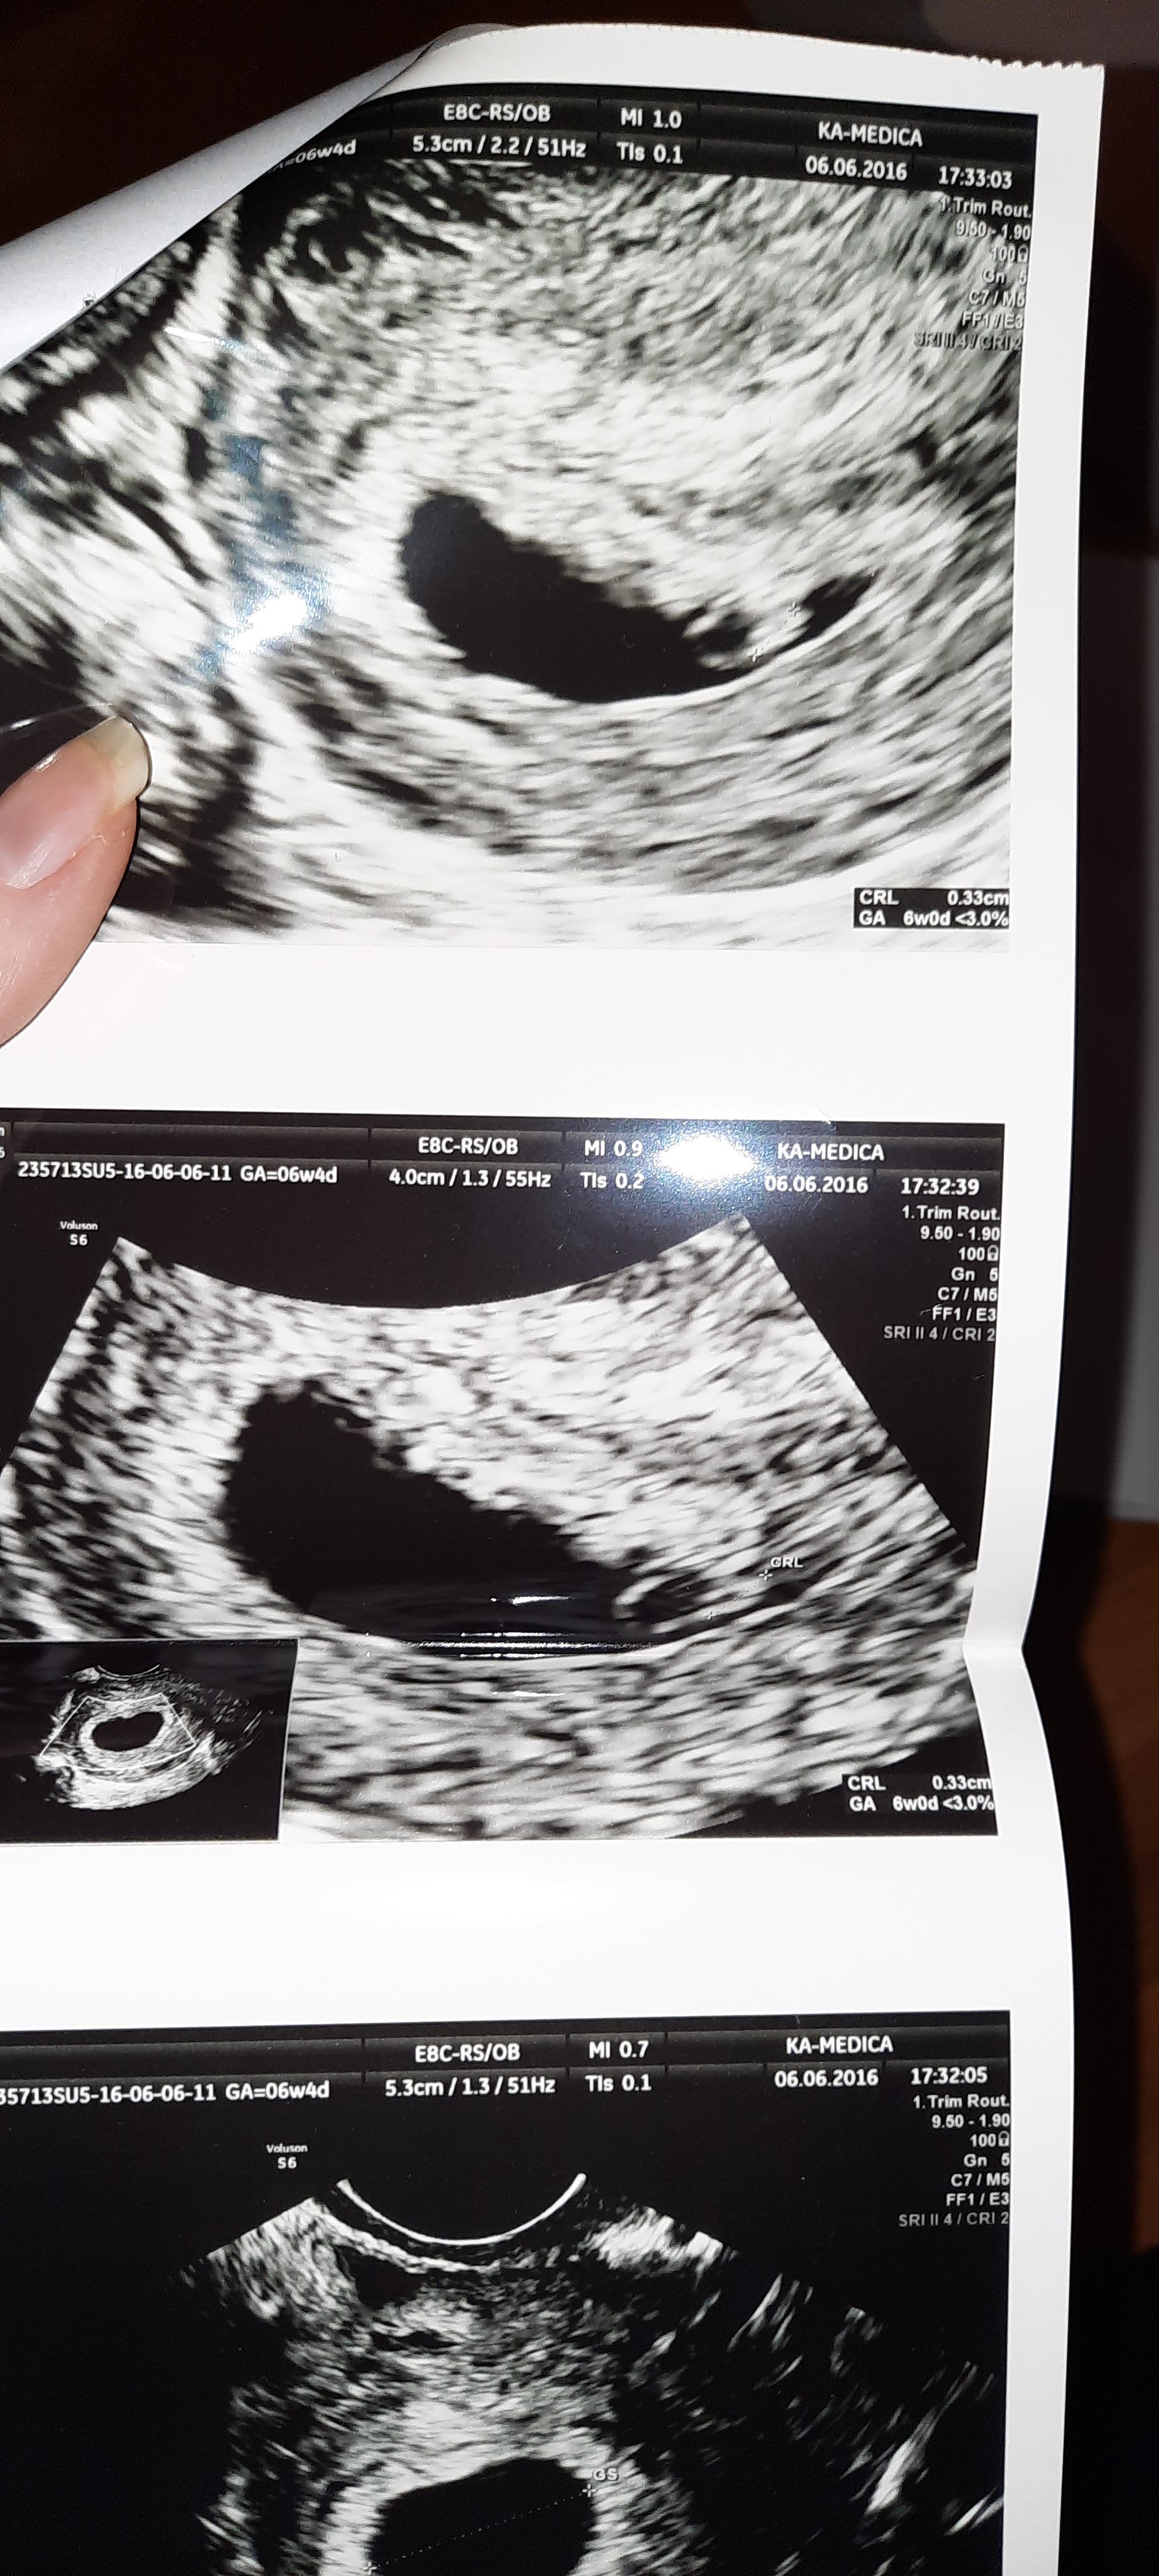

Hej, postanowiłam napisać tutaj, bo jako, że jesteście świeżo w temacie to pewnie się orientujecie. Jestem po 1 poronieniu, obecnie 7t, 0d. ale chyba nie jest dobrze, mam prawdopodobnie za duży pęcherzyk żółtkowy - 5.4mm a pęcherzyk ciążowy jest nieduży, natomiast zarodek CRL 9,1mm.

Bardzo dużo czytałam o tych pęcherzykach żółtkowych i niektore zrodla podaja, ze rozmiar powyzej 5.6mm to juz jest źle, inne ze rozmiar powyżej 6mm zwiastuje coś złego (oczywiscie tez w zaleznosci od tygodnia, pewnie w 11 tygodniu 6mm to jeszcze spoko). Natomiast u mnie to dopiero 7 tydz. 0 d. a skoro juz jest 5.4mm to jak bardzo podrośnie do 10 tygodnia na przyklad :( Dodatkowo mam wrażenie, że lekarz i tak wymierzyl ten pecherzyk tak, ze ma mniejszy rozmiar niz na serio, tzn nie od konca do konca tylko troche jakby ucial (czyli ten rozmiar moglby byc jeszcze wiekszy...):

Zobacz załącznik 1200752

Czy macie może swoje usg z 7 tyg, jakie wymiary miał ten pęcherzyk żółtkowy (oznaczenie YS na usg), napisałam w poradach oddzielny temat ale chyba nikt nie wie o co mi chodzi :( Mam nadzieję, że nie przeszkodziłam Wam tu, że się tak wtrącam nagle w rozmowę, ale już nie wiem co robic. Jestem przerazona, zwlaszcza ze juz 1 poronienie mi się przytrafiło i chyba się załamię jak znów coś będzie nie tak :(

Ogólnie też mi się ten kształt wydaje troche nieregularny, a jak widzę zdjęcia z internetu to są piękne, okrągłe pierścienie i mają cieńsze ścianki :(